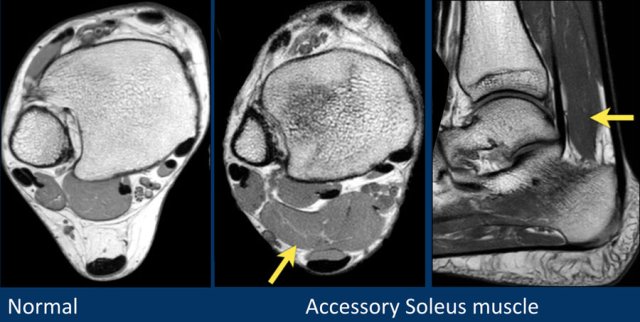

Accessory muscles are frequently seen around the ankle joint.

Since they have a normal signal intensity, they are easily missed.

However when you compare the findings with the normal patient on the left, you will detect the big accessory soleus muscle.

Some examples of accessory muscles.

They are usually asymptomatic, but can be a cause of impingement in specific patient groups (dancers, athletes).

Accessory FHL or FDL are associated with tarsal tunnel syndrome.

The patient on the right has a hypertrophic plantaris muscle.

This can be a cause of Achilles tendinopathy.